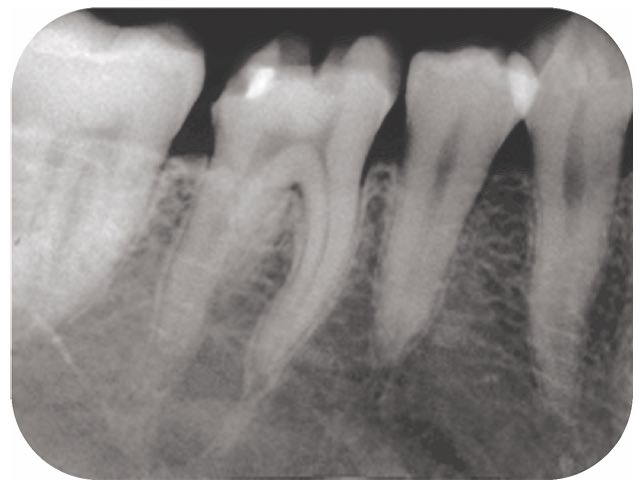

104B-4

35歳の男性。下顎右側第一大臼歯の違和感を主訴として来院した。2週前にう蝕の治療を受け,その数日後から自覚しているという。右下6はレジン系仮封材で充填されており,間欠的な咬合痛と冷水痛とがある。歯髄電気診に反応する。仮封材除去前のエックス線写真と仮封材除去前後の口腔内写真とを別に示す。適切な処置はどれか。1つ選べ

スクリーンショット 2017 01 19 16 07 27

スクリーンショット 2017 01 19 16 07 34a IPC法

b 抜髄法

c 直接覆髄法

d メタルインレー修復

e 光硬化型グラスアイオノマーセメント修復

正答 d

こちらは、歯髄が正常と判断できます。「自発痛」ではなく「間欠的な冷水痛」で、歯髄電気診で反応しているからです。よって、最終的な修復=メタルインレー修復にうつることができます。もちろん、歯髄に近接していて刺激が伝わってしまいそうなときには、間接覆髄や裏層などお薬をつめることを途中ではさむかもしれませんが、大枠の治療方針としてはメタルインレー修復が妥当となります。問題文の冷水痛が、自発痛だったりすると、「歯髄鎮静療法」や「抜髄」を考えていかなければならなくなります。